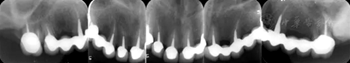

患者采用正確的口腔衛(wèi)生措施維護(hù)口腔健康,每半年至1年進(jìn)行1次牙周維護(hù)。隨訪觀察9年,臨床及影像學(xué)檢查均顯示治療效果穩(wěn)定,患者對口腔健康、功能及美觀均滿意(圖8,圖9)。

圖8 患者治療后9年臨床照片 A:正面微笑像;B:前牙像

圖9 患者治療后9年上頜牙列根尖X線片